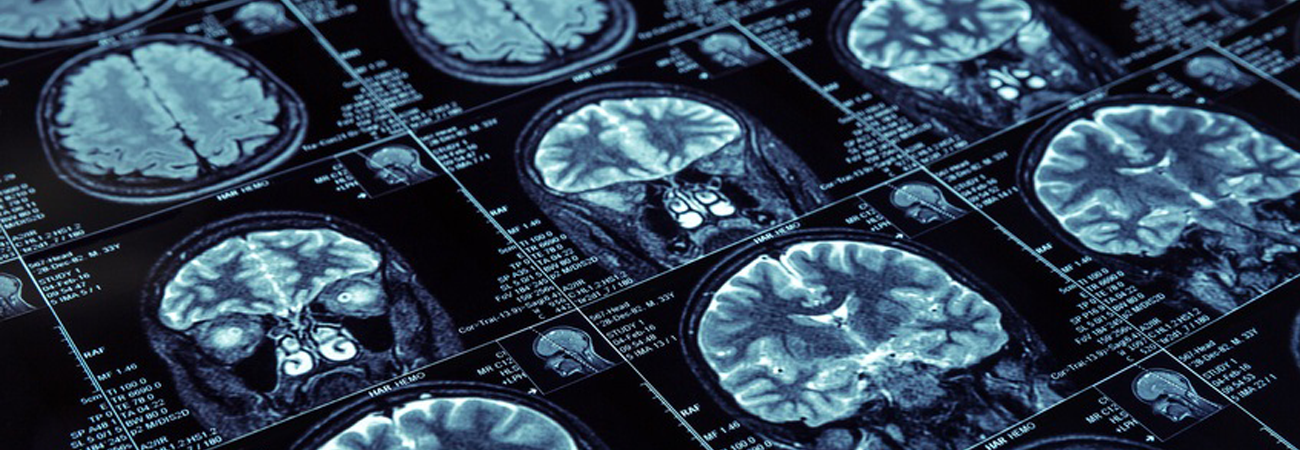

KI wertet CT-Bilder aus

Seit wenigen Jahren gibt es die Möglichkeit, den Schlaganfall-Zeitpunkt nach Aufnahme eines Computertomografen zu schätzen. Bei dieser so genannten "Netto-Wasseraufnahme-Methode" wird die Dichte des geschädigten Hirngewebes gemessen und mit gesundem verglichen. Ein Team von Informatik-Fachleuten aus München, London und Edinburgh hat jetzt mithilfe künstlicher Intelligenz (KI) eine Software entwickelt, die diese Dichtemessung mit weiteren Bildmerkmalen kombiniert, die für das menschliche Auge bisher nicht erkennbar waren. Die Forschenden haben ihr Programm an CT-Bildern von fast 2.000 Patientinnen und Patienten getestet. Ihre Diagnose war dabei doppelt so genau wie die bisherige Methode.